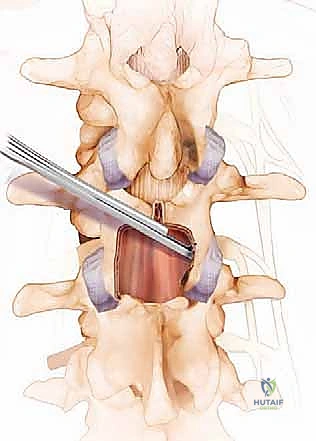

- استئصال الصفيحة الفقرية (Laminectomy): هي الجراحة الأكثر شيوعاً. يتم فيها إزالة الصفيحة الفقرية (سقف القناة الشوكية) بالكامل، مع إزالة الأربطة المتضخمة والنتوءات العظمية لفتح مساحة واسعة للأعصاب.

- استئصال جزئي للصفيحة (Laminotomy): جراحة أقل توغلاً، يتم فيها إزالة جزء صغير فقط من الصفيحة الفقرية لإنشاء نافذة لتخفيف الضغط في نقطة محددة.

- توسيع الثقبة العصبية (Foraminotomy): يتم التركيز على توسيع الفتحة الجانبية التي يخرج منها جذر العصب.

- تخفيف الضغط (Decompression): باستخدام أدوات مجهرية دقيقة وحفارات عالية السرعة (High-speed burrs)، يتم إزالة النتوءات العظمية، وجزء من الصفيحة الفقرية، والرباط الأصفر المتضخم. يتم ذلك بحذر شديد مليمتر بمليمتر حتى يتم تحرير كيس الجافية (الذي يحوي الأعصاب) وجذور الأعصاب بالكامل.